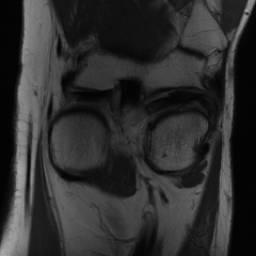

5.3 Out-of-Domain Generalisation

One way to test the generalization capability of the trained X-Diffusion is to test it on a completely different domain from an MRI dataset not seen during training. We report the single-slice results on NYU fastMRI [37, 82], a knee MRI dataset, using the X-Diffusion trained on the BRATS brain MRIs. The results are shown in Figure 9 and Table 2. It shows how successfully X-Diffusion is able to generate knee MRIs from a single image, despite not seeing knees at all in training. To qualitatively assess how realistic our generated 3D volumes were (produced from a single slice), we gave 20 generated examples alongside their real MRI counterparts to an expert orthopaedic surgeon. He was then asked to identify the real example from a given pair. The surgeon identified with certainty only 10 real knee MRIs out of 17, while could not decide on the remaining 3 of the 20 MRI pairs. This further validates the generated out-of-domain MRIs.